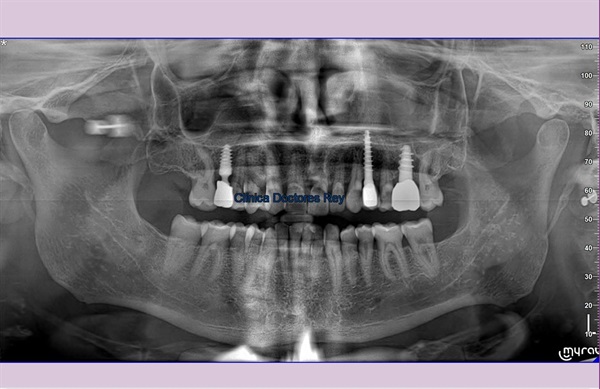

Paciente adulto 66 años, padeció infarto de miocardio, empresario, viaja mucho, conduce mucho tiempo coche, perfeccionista, rigurosamente estricto y preocupado por sus clientes. Consulta por implante dental para zona edéntula en maxilar superior . Le preocupa el espacio edéntulo de un maxilar. Facetas de desgaste, pérdida ósea actual con tratamiento periodontal antiguo, molestias ligeras al masticar, apretador movilidad dental. Discurrir sobre el tratamiento es interesante para dar respuesta a una combinación de hechos asociados derivados de un estado DE PARAFUNCIÓN NEUROMUSCULAR.